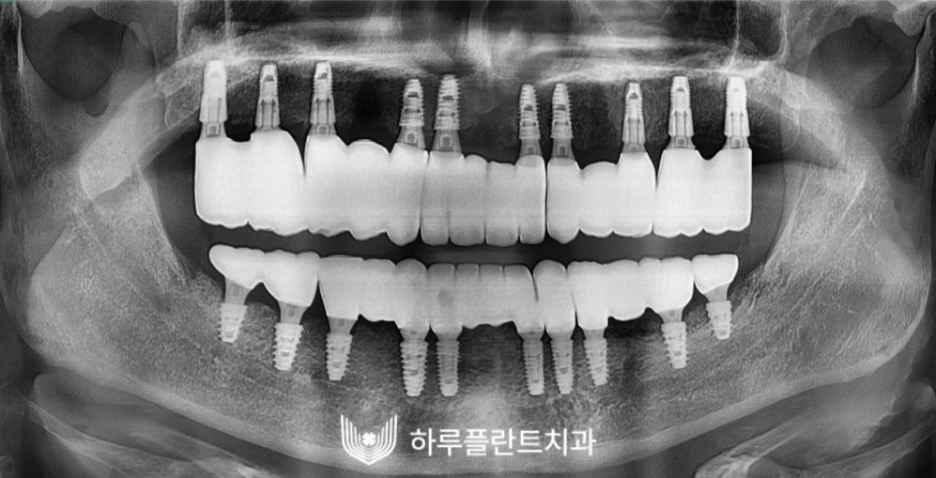

2022.03

고난도 뼈이식 후 전체 임플란트가

훌륭하게 마무리 되었습니다.

난이도 높은 전악임플란트가

성공적으로 마무리 된 후 의 구강 사진입니다.

치아의 기능은 물론 심미성까지

완벽히 회복된 모습이죠.